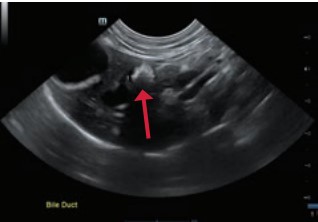

Hình ảnh siêu âm trên gan mèo cho thấy giãn ống mật do sỏi kích thước lớn

Chất khoáng tăng âm trong lòng cổ túi mật và ống mật chủ (mũi tên đỏ). Phía xa trường siêu âm có xuất hiện các dải bóng âm